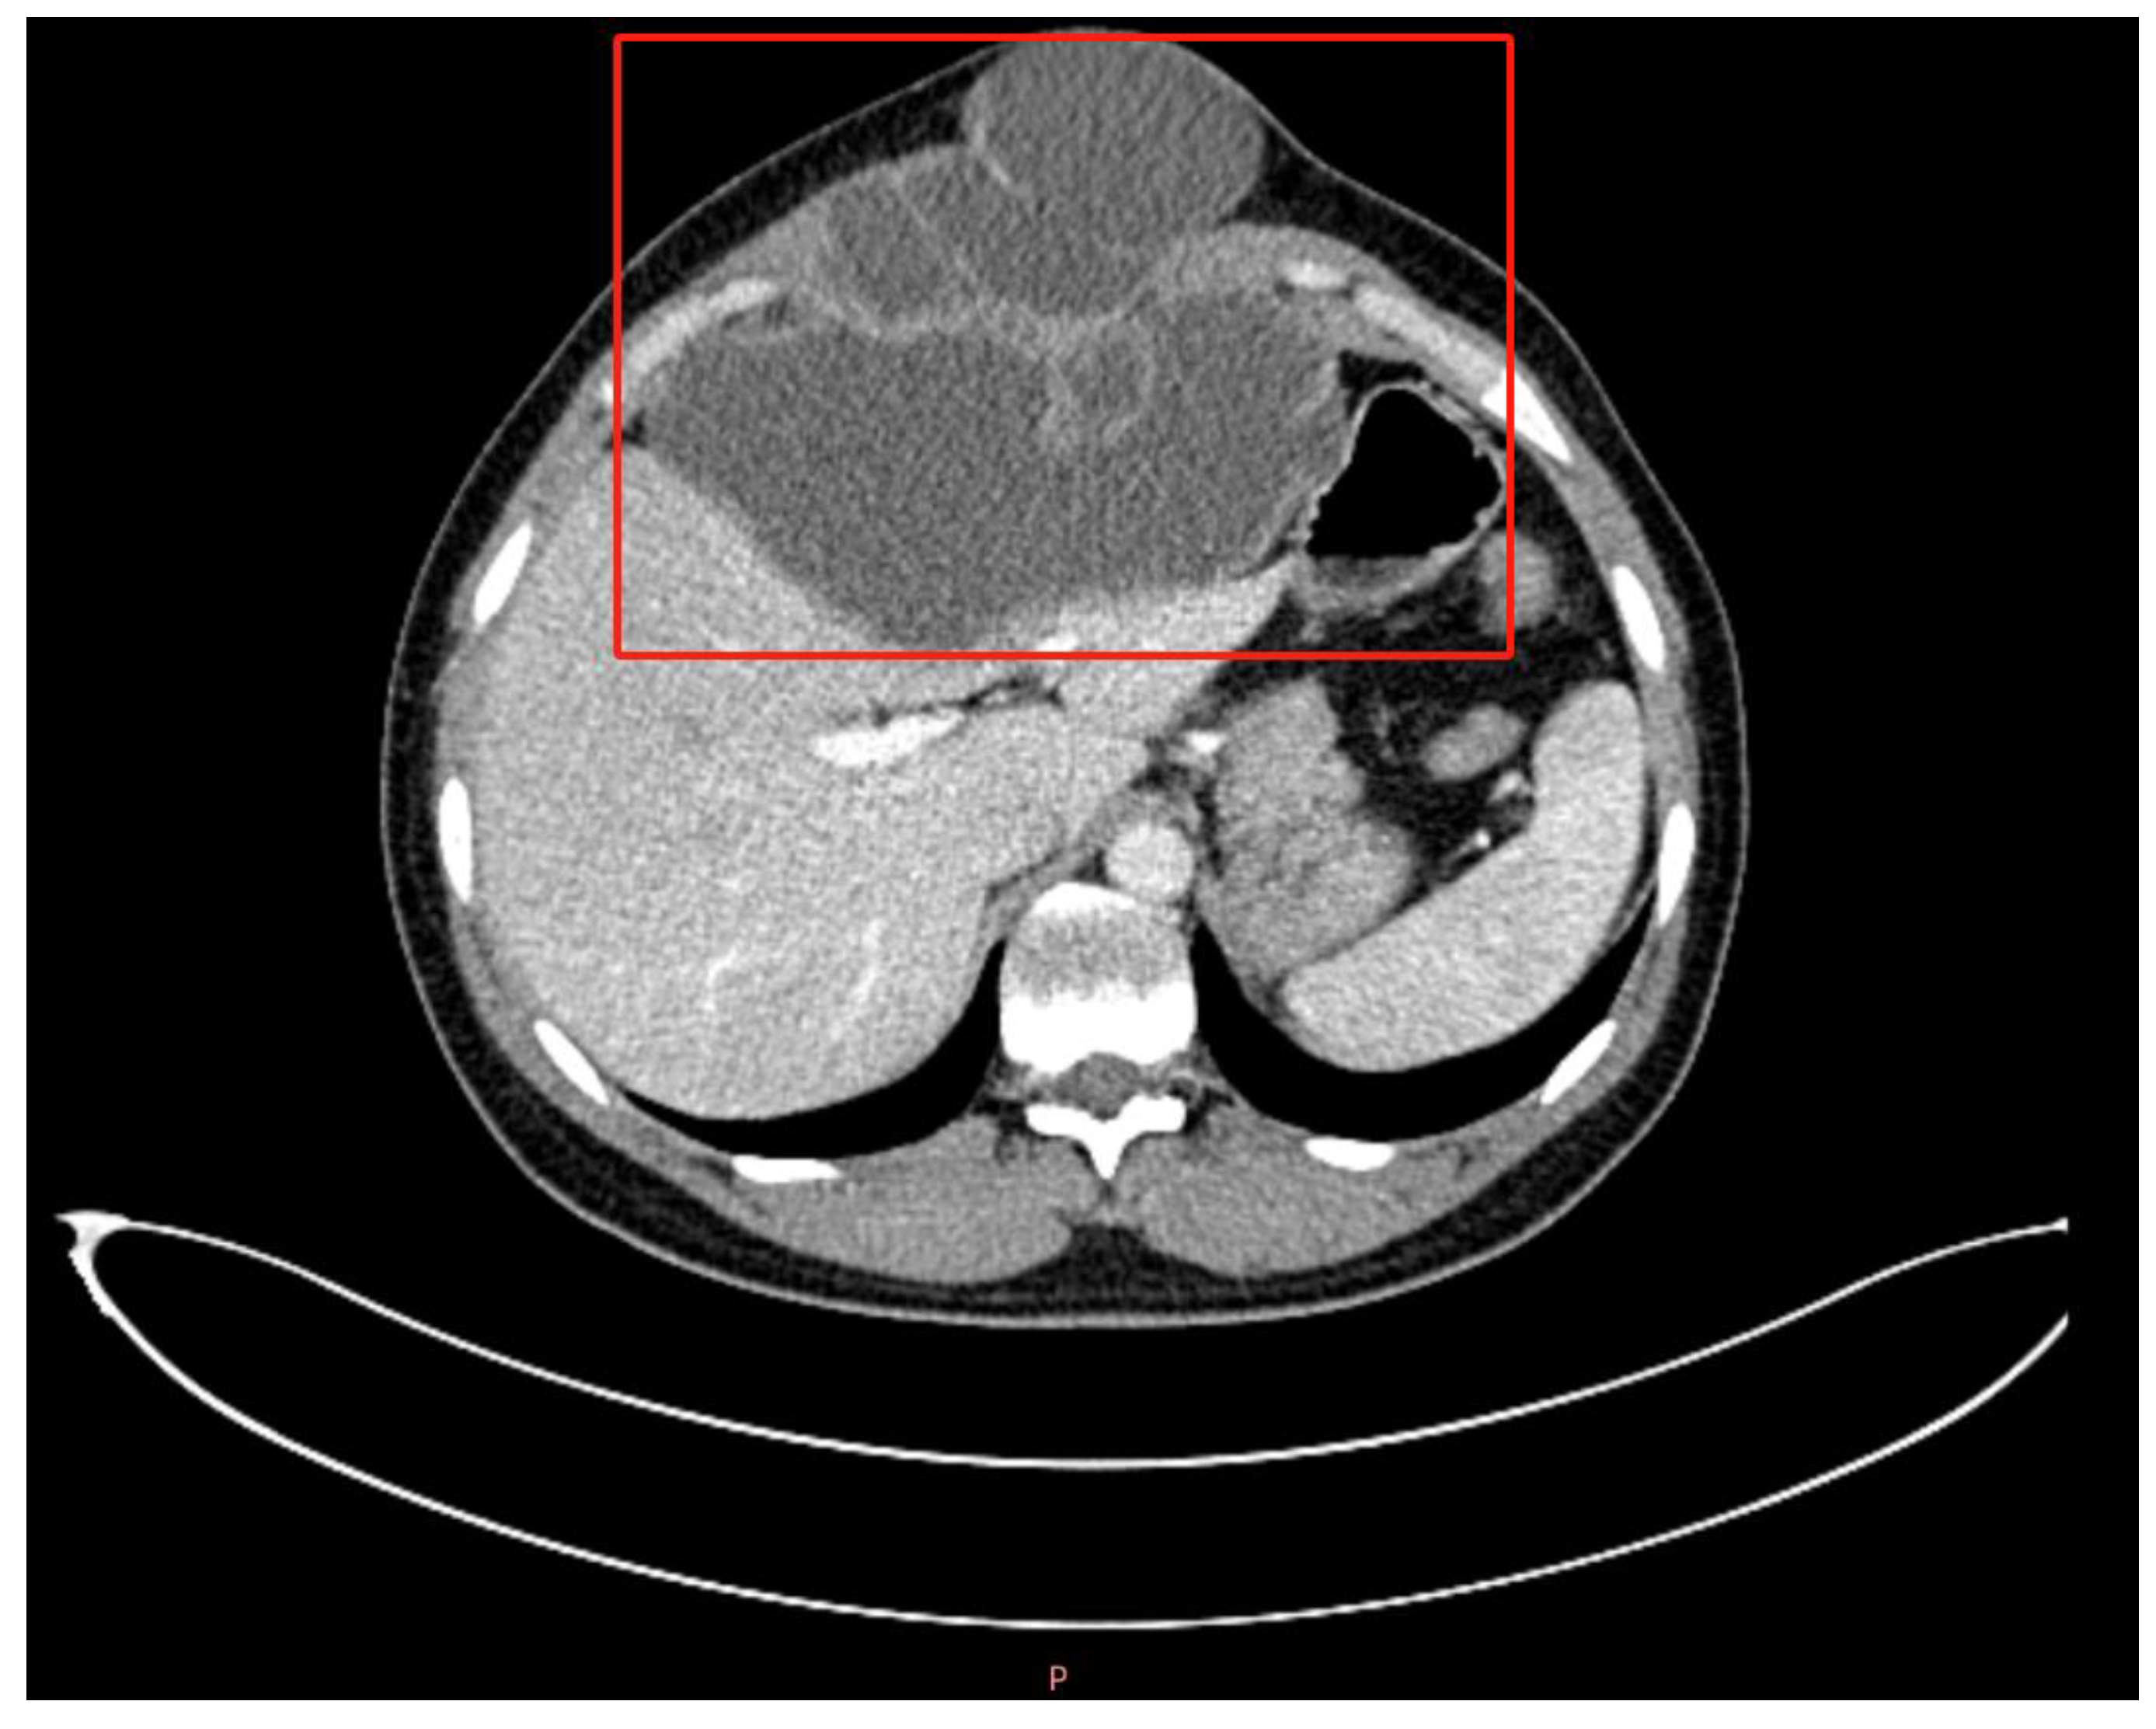

2.2. Investigations and Differential Diagnosis

3.1.3. The Difference between CE and AE in Imaging and Pathology